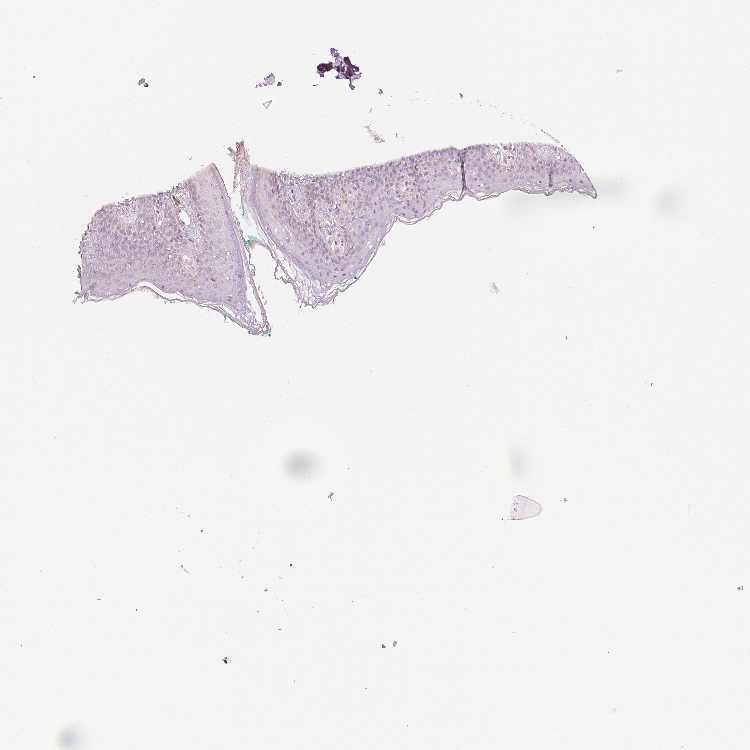

OR13C3